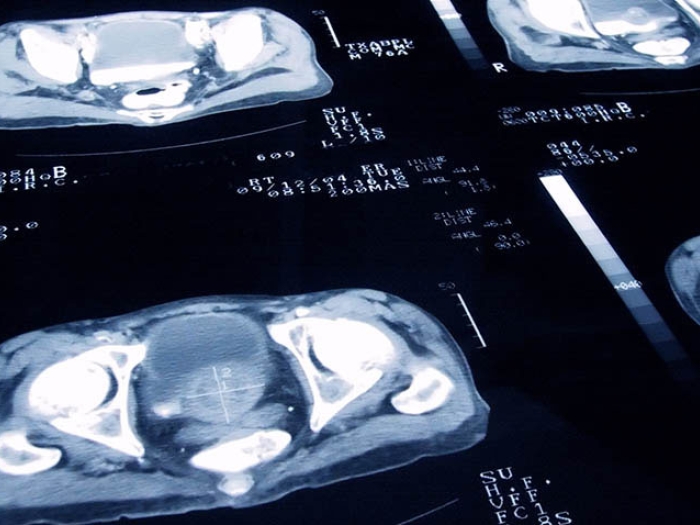

Prostate cancer scans

Health Lab

How Should Radiation Oncologists Manage Prostate Cancer Patients During the COVID-19 Pandemic?

An international team of radiation oncologists are helping to protect patients and providers and conserve protective equipment for frontline health care workers during the COVID-19 pandemic.